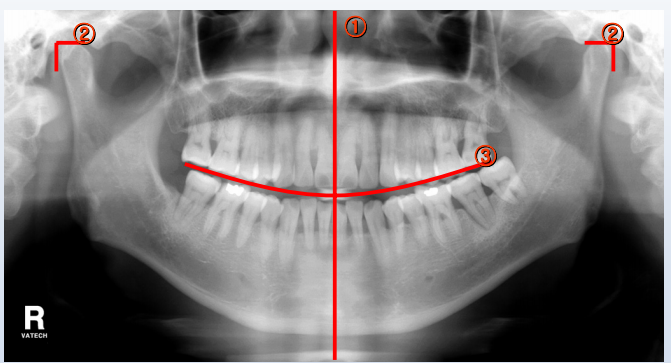

올바른 파노라마 영상 (축소/확대/흐릿/어두움)

<올바른 파노라마 영상>

- 전치부가 화면의 센터 수직라인과 일치해야 함

- 좌우 TMJ의 높이 및 여백이 같아야 함

- 교합면의 스마일라인이 완만한 곡선을 이루어야 함